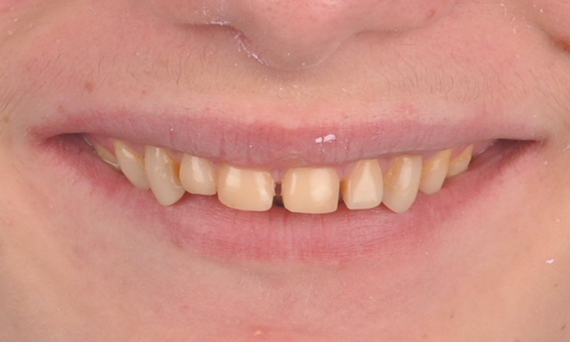

Minimal Preparation Veneers after Trauma of Upper Central Incisors

Restoration with a highly esthetic material in one day after trauma to the maxillary central incisors.

Before: Clinical Situation pre-op. Trauma of upper central incisors

After: Adhesively bonded restorations.

Dr. Mohamed Hassanien

Cairo, Egypt